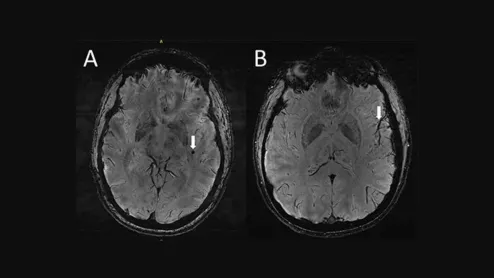

Ultra-high-res MRI Reveals Migraine Brain Changes